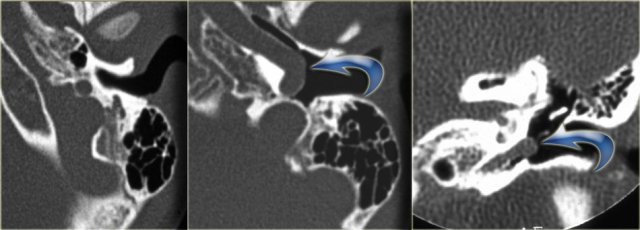

On the left a 2-year old girl.

The images are of a CT-examination is done prior to cochlear implantation.

A minor deformity of the cochlear apex is visible – there is no separation of the second and third turn and the bony modiolus is absent.

The vestibular aqueduct is normal.

On the left a 10-year old boy, scheduled for cochlear implantation.

There is a widening and shortening of the lateral semicircular canal.

The vestibule is relatively large (arrow).